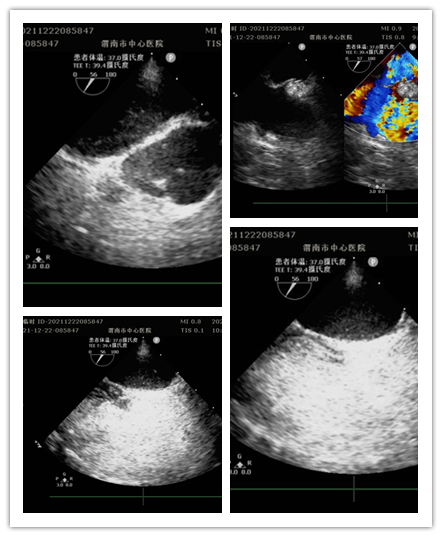

12月22日上午,江南在线体育超声科门诊完成全市首例经食管超声心动图。这是继完成30例术中经食管超声心动图之后首次在门诊进行。此项检查填补了渭南市超声诊疗空白,标志着医院心血管诊疗技术迈向新台阶。

患者女性,13岁,因间断眩晕1年,加重伴头痛20余天就诊于医院全科医学科。住院期间,行经胸超声右心声学造影提示存在心内分流,为进一步明确心脏疾病,行经食管超声心动图检查。检查前,超声科杨玉萍医师对患者充分评估,与刘晓晖主任共同商定患者检查方案,进行充分准备。为保障小患者安全,全科医学科副主任医师苗娟妮、心脏外科副主任姜永红及团队全程参与。在多名医护人员的通力协作下,成功为患者行经食管超声检查。检查过程顺利,患者无不良反应,最终明确超声诊断,为患者进一步治疗提供了有力依据。

经食管超声心动图检查是将超声探头插入食管,直接贴在心脏的后方,从后向前观察心脏、血管和血流动力学情况,避免了气体及脂肪的干扰。加之食道超声的探头频率高于普通经胸超声探头,所以能扩大心脏的扫查范围,提高图像质量及细微分辨率。主要运用于术前评估、术中监测、术后复查,尤其是对经胸超声心动图检查成像困难或有关结构显示不清,致使诊断难以明确的各种心脏或大血管疾病患者,能更加准确地诊断心脏细小病变及疑难疾病。特别是能有效评估房颤患者血栓形成的危险性并作为可靠依据,对房颤治疗前期评估具有重要意义。